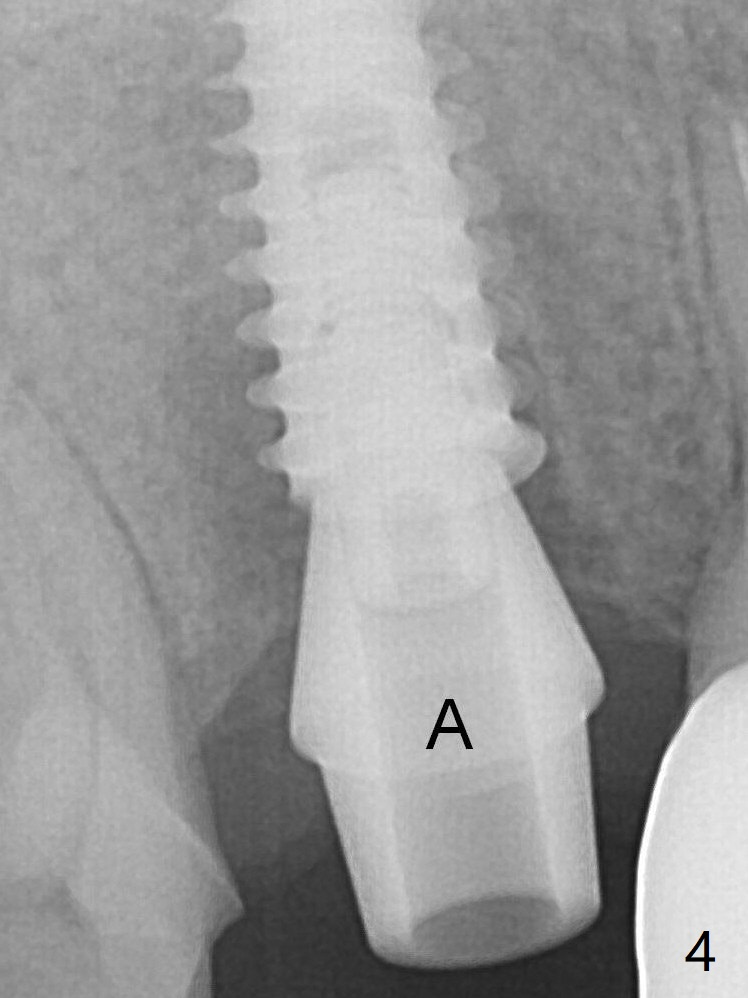

To reduce the gap and periimplantitis, a 5x11 mm IBS implant is placed with insertion torque > 50 Ncm after further osteotomy using Magic Drills (Fig.4). Following placement of 5.5x4(4) mm abutment (A), a splinted provisional is fabricated at #3 and 4. The provisional is stable 3 months postop (Fig.7). Bone graft appears to remain between the implant fins (arrows). The bone density of the bone graft between the implant fins increases 4.5 months postop (Fig.9). The bone density appears to reach the normal value (same as that of the nearby bone) 1 year 3 months post cementation (Fig.11).